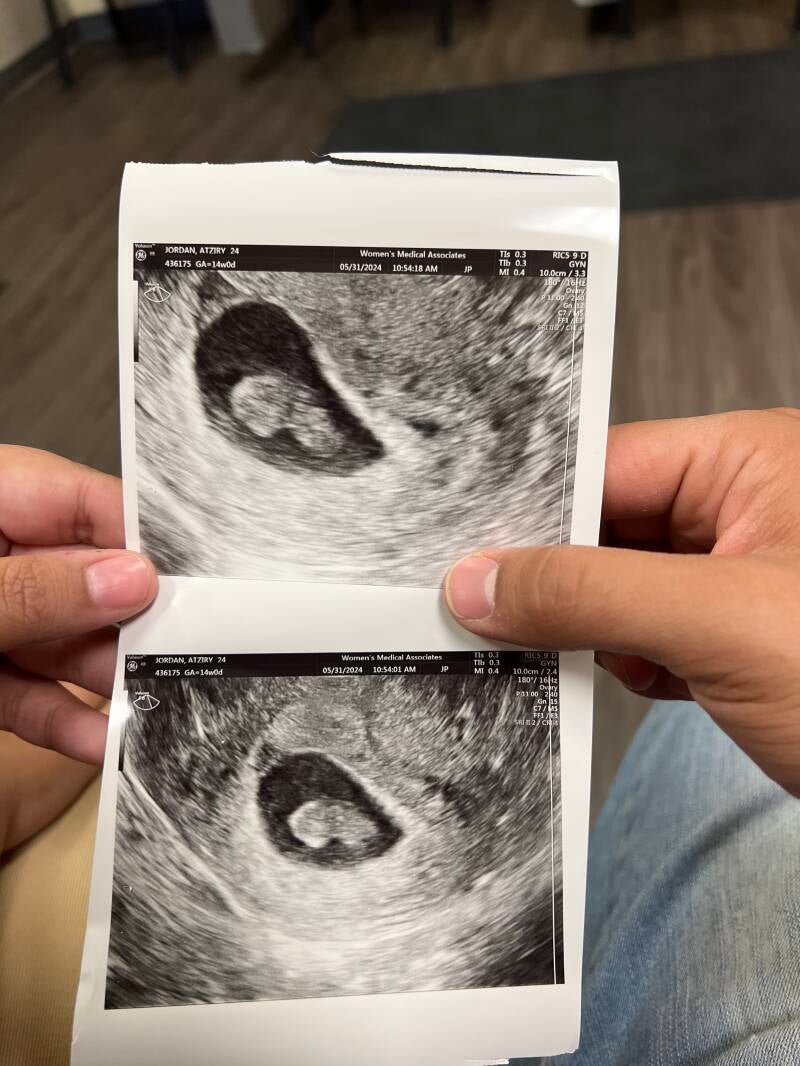

We were thrilled (and nervous) to find out we were pregnant with our second baby in April of 2024. We had a short time to enjoy telling our family, friends and most importantly our son that he would be a big brother. Our ultrasounds had shown little promise as my uterus appeared empty, but finally on May 30th there was our little baby! We experienced a brief moment of pure bliss before realizing our ultrasound tech was concerned and her face told me what my heart could not accept. “There is a baby, but there is no cardiac activity.” The room felt painted with grief, confusion and anger and the silence as she tried to scan for a heartbeat resulted in my stifled tears and willing our babies heart to beat again. We decided to name baby, who we will never know if they were a boy or girl, Aislin Almos, the meaning basically was that our baby is our sleepy dream, only a vision of the life we imagined we’d have. We’ve navigated our grief while also trying to be the best for our toddler, he often tells us he is playing with his “baby sister” and we find peace that somewhere, in another version of us, we are whole and complete. My heart and love are with parents who’ve lost their children, lost sight of their plans of their future and who are moving through this journey!